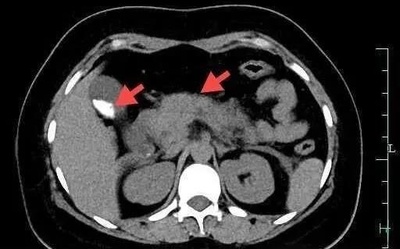

カニを一気に4杯食べた女性 急性膵炎で夜中に救急治療